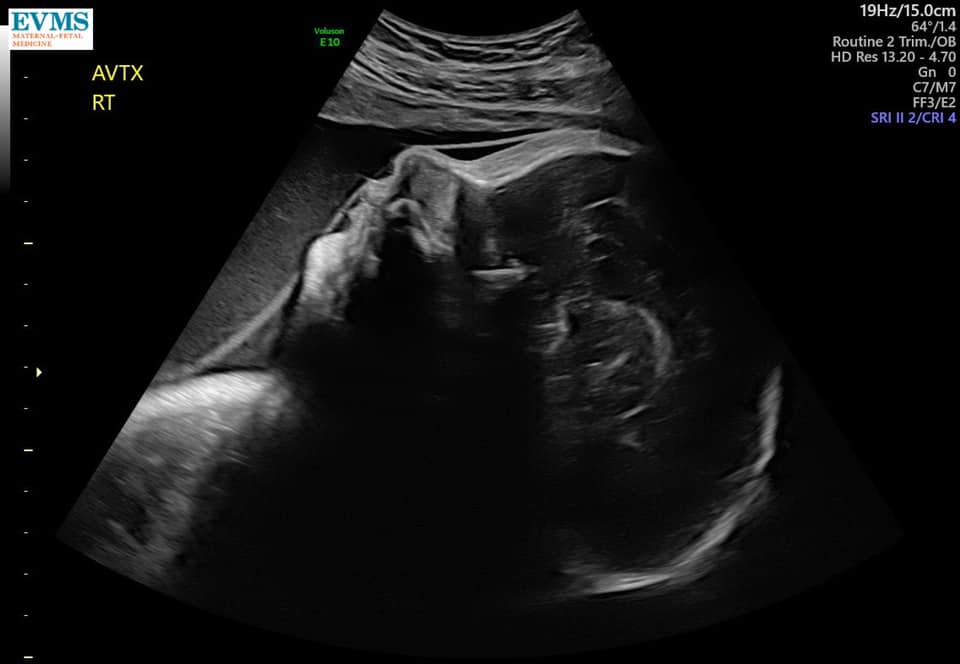

Ultrasound Photos at 32 Weeks Pregnant With Twins